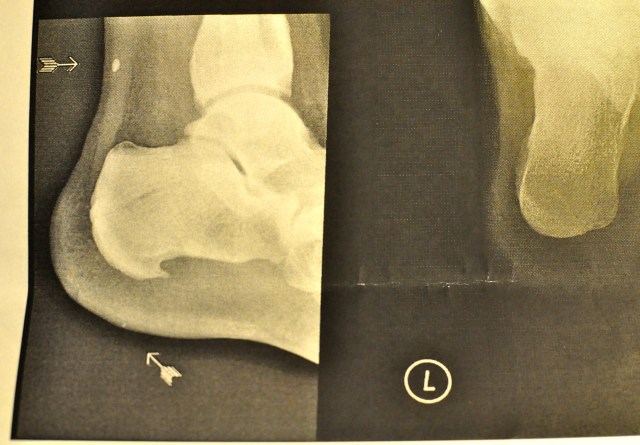

I also became unable to walk. Any pressure on my left heel caused pain. No external signs of putrefaction. I go to a clinic whereupon very smart doctor cries “Spicula!” It is perhaps his only word in English.

It appears that I have a rose-thorn-like thing-spiculum- growing out of my heel bone. This is messing with the tendons causing the pain.

They seem to have stolen my Xray photo.

Your X-ray purloined by the BMJ too, must be a good one. I find the constant harping on about BMI and weight quite tedious.